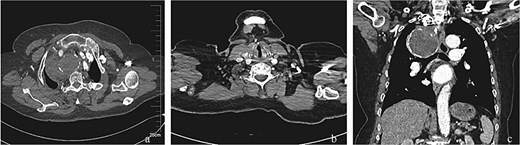

A 75-year-old female patient was admitted because of intermittent chest pain and dyspnea for 2 weeks. A thoracic aorta computed tomography angiography (CTA) demonstrated a large right proximal SAA with partial thrombosis, and the adjacent trachea, esophagus, and blood vessels were obviously compressed and displaced (Fig. 1). Physical examination revealed wheezing and phlegm sounds in the chest, and no obvious pulsatile mass was found in the right supraclavicular fossa.

Radiologic characteristics of the SAA. (a) Axial CTA demonstrates a bipartite aneurysm morphology with superior–inferior compartmentalization. The inferior spherical component measures 70.05 mm (long axis) × 69.73 mm (short axis), exhibiting regular contour and homogeneous attenuation. (b) The superior ellipsoid component displays dimensions of 51.81 mm (long axis) × 35.59 mm (short axis), with peripheral thrombus formation. (c) Coronal reformation reveals the characteristic gourd-shaped configuration and intraluminal thrombus burden. (d and e) Volume-rendered reconstructions delineate circumferential calcifications along the aneurysm wall, particularly prominent at the inflow/outflow transitional zone.